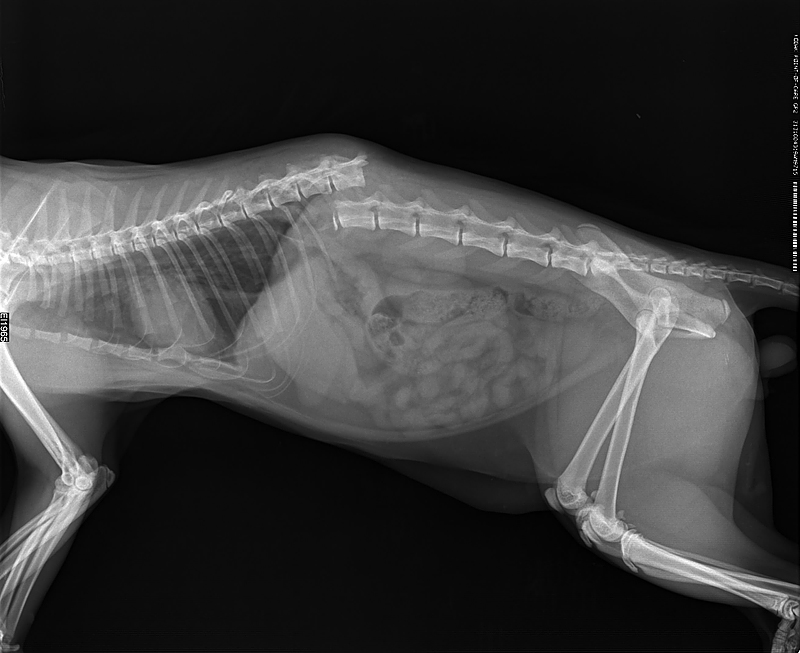

Раздел: Снимки-откровения